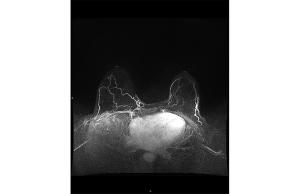

These ten images can help ob/gyns recognize the additional information GBCA administration provides in MRIs.

Gadolinium-based intravenous contrast agents (GBCA) provide additional information based on signal intensity changes after GBCA administration.